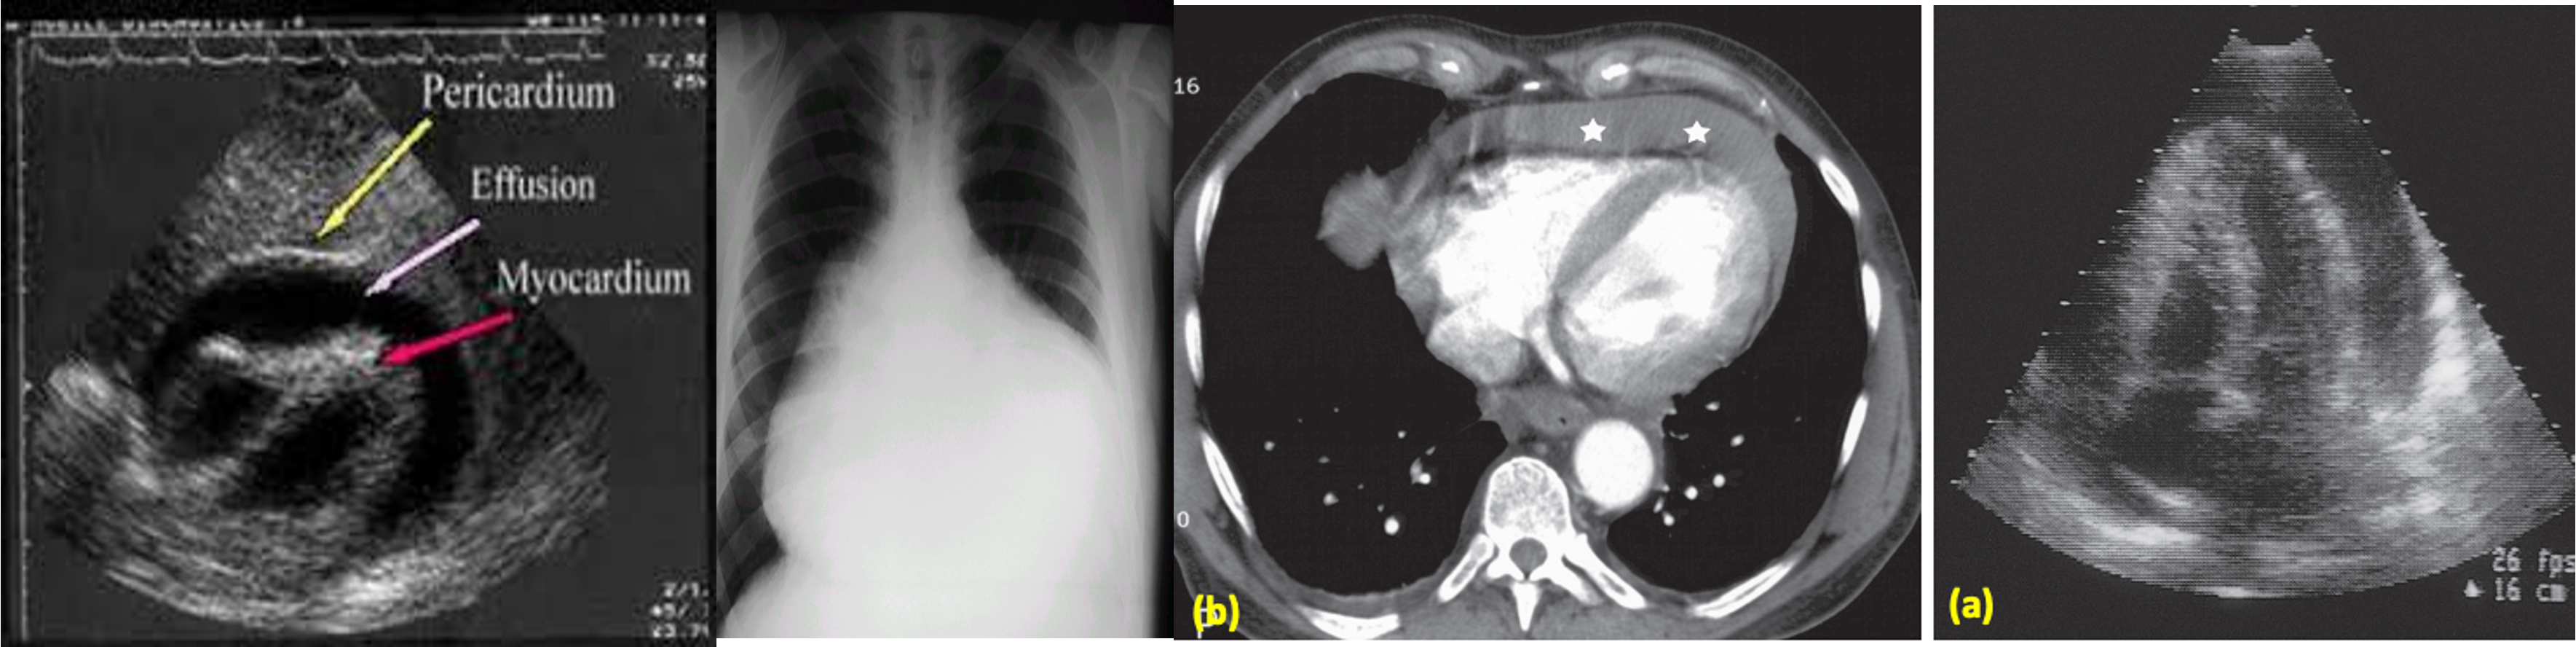

The heart is greatly enlarged. The outline is well defined and the *shape globular. The lungs are normal.

a) Large pericardial effusion on an apical four-chamber view echocardiogram.

b) CT scan showing fluid density (stars) in the pericardium.